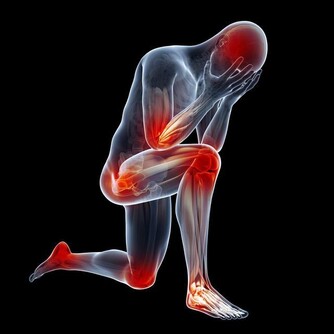

黃帝答曰:“你知道什麼叫慢性病嗎?慢性病就是因為生活方式、生活環境、精神心理脫離正常的軌道,違反自然規律,日積月累,造成身體器官功能的下降、衰退的結果。只有重新回歸天道,讓身體重新獲得自我修復的條件,才會有康復的可能。西醫的所有工作都集中在代替器官功能發揮作用上。比如糖尿病,不是修復胰臟,而是人工注射胰島素,久而久之胰臟就徹底失去功能;比如腎病,不是修復腎臟,而是代替腎臟進行洗腎、透析,最後的結果就是腎臟壞死。如此不一而足,西醫所有的治病邏輯都是這樣的,因此最終結果是慢性病都成了不治之症,只能終身服藥。

西醫的檢查是病變的結果檢查,只有到了身體通過量變的積累達到了質變時候才能檢查出來。這是為什麼有的人心悶、頭痛全身不舒服,到醫院卻什麼也檢查不出來的道理。這就是為什麼癌症只有到了晚期才能檢查出來的原因,因為早期不叫癌症,早期就叫高血壓、糖尿病、腎炎、乙肝、風濕、哮喘、附件炎等等。"